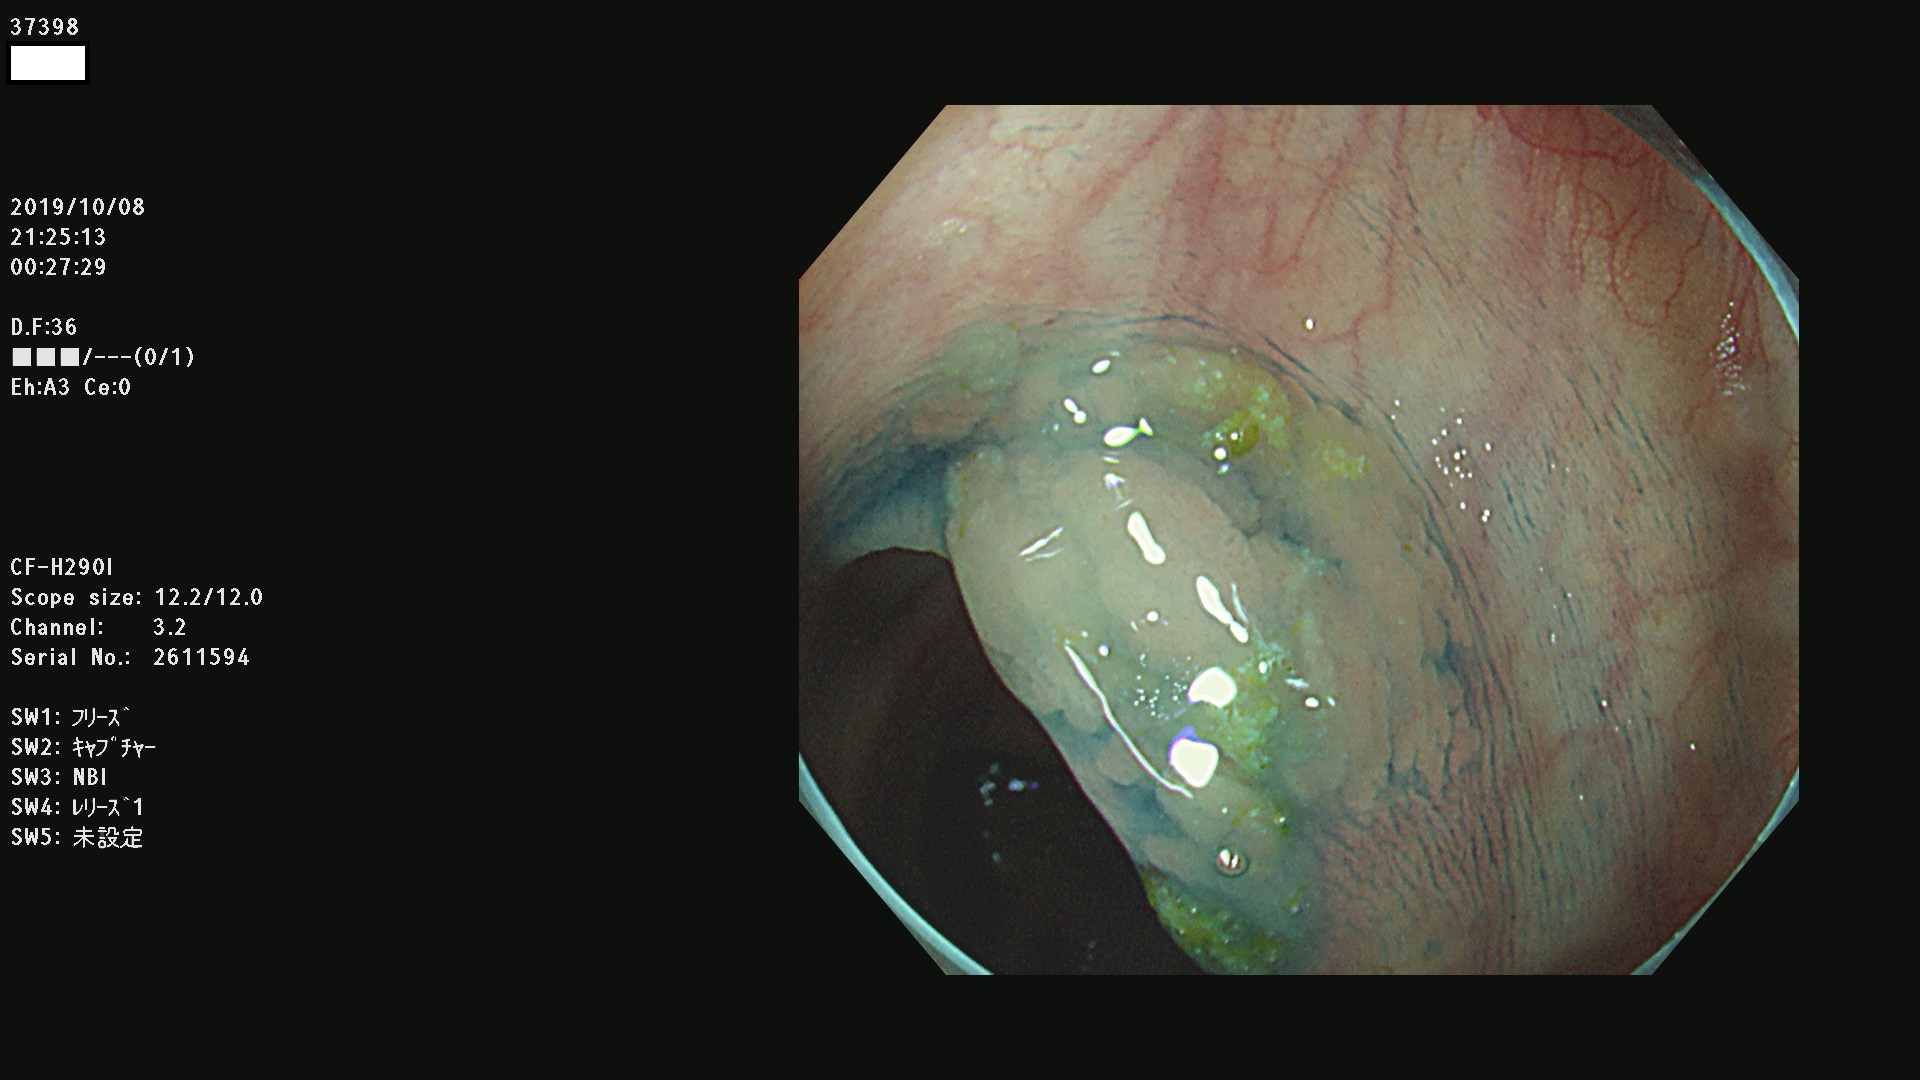

37300(SSAPのみ) 37301 37303 37304 37306 37307 37308 37309 37312 37313 37315(SSAPのみ) 37316 37317(SSAPのみ) 37319 37321(SSAPのみ) 37322 37323 37324 37325 37326 37328(SSAPのみ) 37329 37330 37331 37332(SSAPのみ) 37333 37334 37336 37337 37338 37340 37342 37343(SSAPのみ) 37344 37345 37346 37347 37348 37352(SSAPのみ) 37353 37354 37355 37356 37358 37360 37361(SSAPのみ) 37362 37363 37366 37367 37369 37370 37371 37372(SSAPのみ) 37375 37376 37377 37380 37381(SSAPのみ) 37382 37383 37384 37385(SSAPのみ) 37386 37387 37388 37389 37390 37392(SSAPのみ) 37393 37394 37395 37396(SSAPのみ) 37397 37398(SSAPのみ) 37399

発見困難で危険性の高い平坦型病変(上記100名より抽出) )